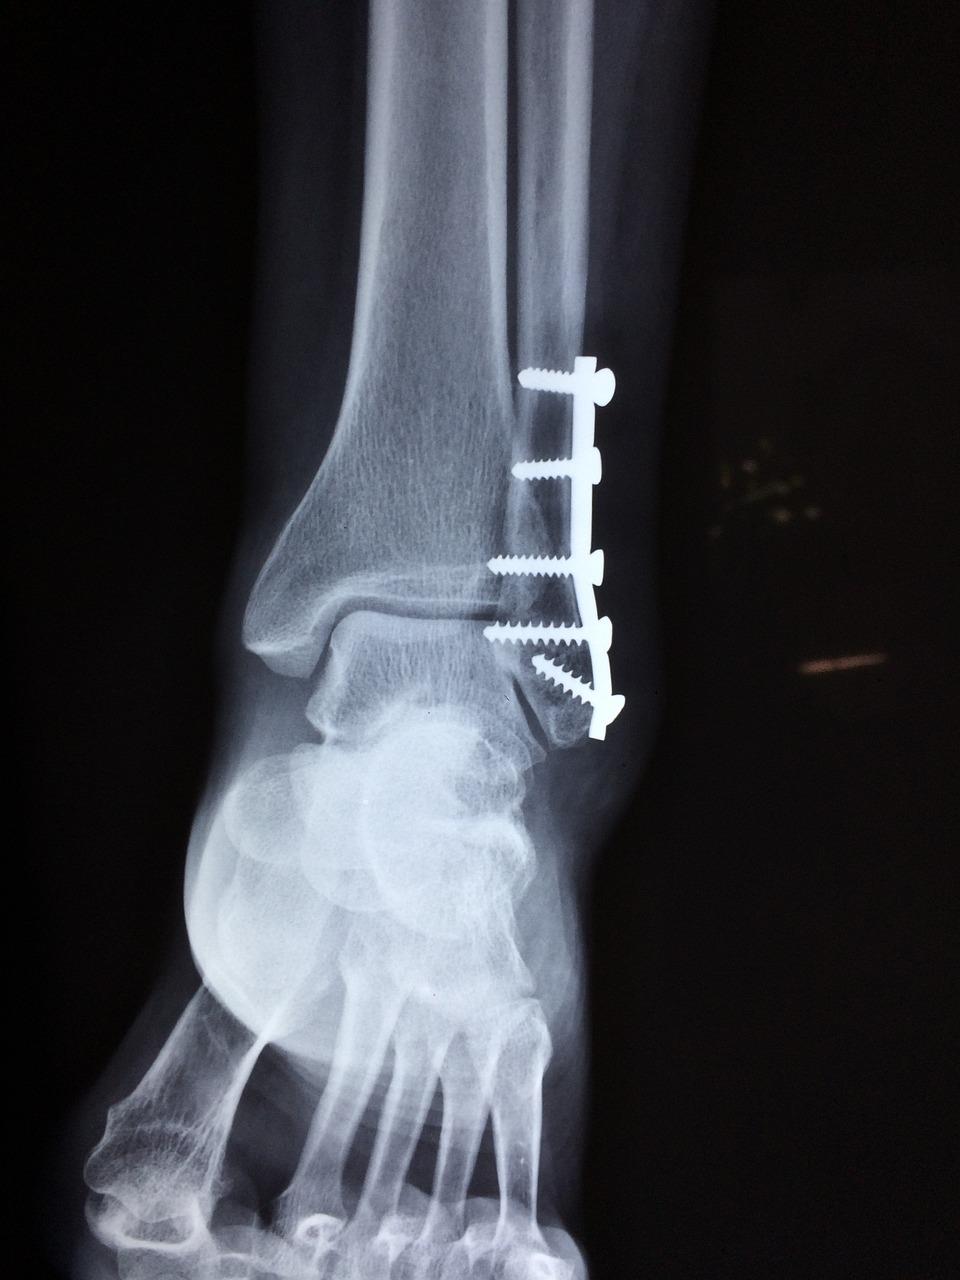

Orthopedische chirurgie voor fracturen en botbreuken

Orthopedische chirurgen in Delft bieden gespecialiseerde zorg voor fracturen en botbreuken. Met geavanceerde technieken en ervaring streven zij naar nauwkeurige herstelprocedures voor optimale genezing.

Van complexe breuken tot acute verwondingen, deze specialisten hebben de expertise om de juiste benadering te kiezen voor elke situatie. Vertrouw op hun vaardigheden voor een doeltreffende behandeling en revalidatie.

De focus ligt op het herstellen van functionaliteit en mobiliteit na een trauma. Ontdek de hoogwaardige orthopedische chirurgie die beschikbaar is in Delft voor een snel en effectief herstel.

Orthopedie in Delft: Voet en enkelzorg bij orthopedische praktijken

Voor uitgebreide voet- en enkelzorg ben je bij orthopedische praktijken in Delft aan het juiste adres. Van complexe aandoeningen tot dagelijkse klachten, deze specialisten bieden op maat gemaakte behandelingen voor een optimale mobiliteit.

Met geavanceerde diagnostiek en multidisciplinaire benaderingen streven zij naar duurzame oplossingen voor voet- en enkelproblemen. Ontdek innovatieve behandelopties om pijn te verlichten en functionaliteit te herstellen.